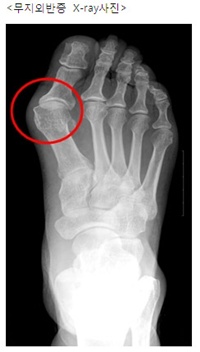

무지외반증은 엄지 발가락이 두 번째 발가락 쪽으로 휘어진 질환이다. 앞이 좁고 굽이 높거나 발가락을 꽉 죄는 구두를 신을 경우 발끝이 조여 지면서 무게 중심이 앞으로 쏠려 발가락에 압력이 가해지며 발병한다. 휘어진 뼈 때문에 외관상 좋지 못할 뿐만 아니라 변형이 심하면 무릎과 엉덩이 관절, 허리까지 통증을 유발하고, 보행 장해로도 이어질 수 있다.